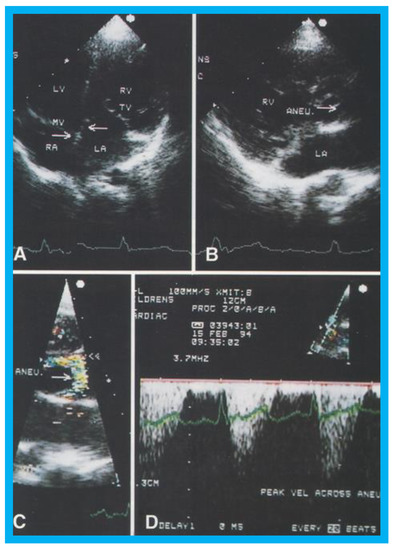

Figure 17. (A) Selected video frame from apical four chamber projection indicating reversal of the ventricles: The attachment of the mitral valve (MV) leaflet is higher than that of the tricuspid valve (TV), suggesting that the morphologic right ventricle (RV) is on the left side and that the morphologic left ventricle (LV) is on the right side. The right atrium (RA) drains into morphologic LV, and the left atrium (LA) is connected to the morphologic RV. Also note that the medial leaflet of the TV is plastered on to the ventricular septum suggesting Ebstein’s type of morphologic TV. (B,C) Selected video frames from parasternal long axis view demonstrate the aneurysm (Aneu) with color-Doppler turbulence (C). (D) This frame shows a high peak Doppler flow (3.5 m/s), which indicates a peak instantaneous gradient of 49 mmHg. Reproduced from Reddy S.C.B., et al. [22].